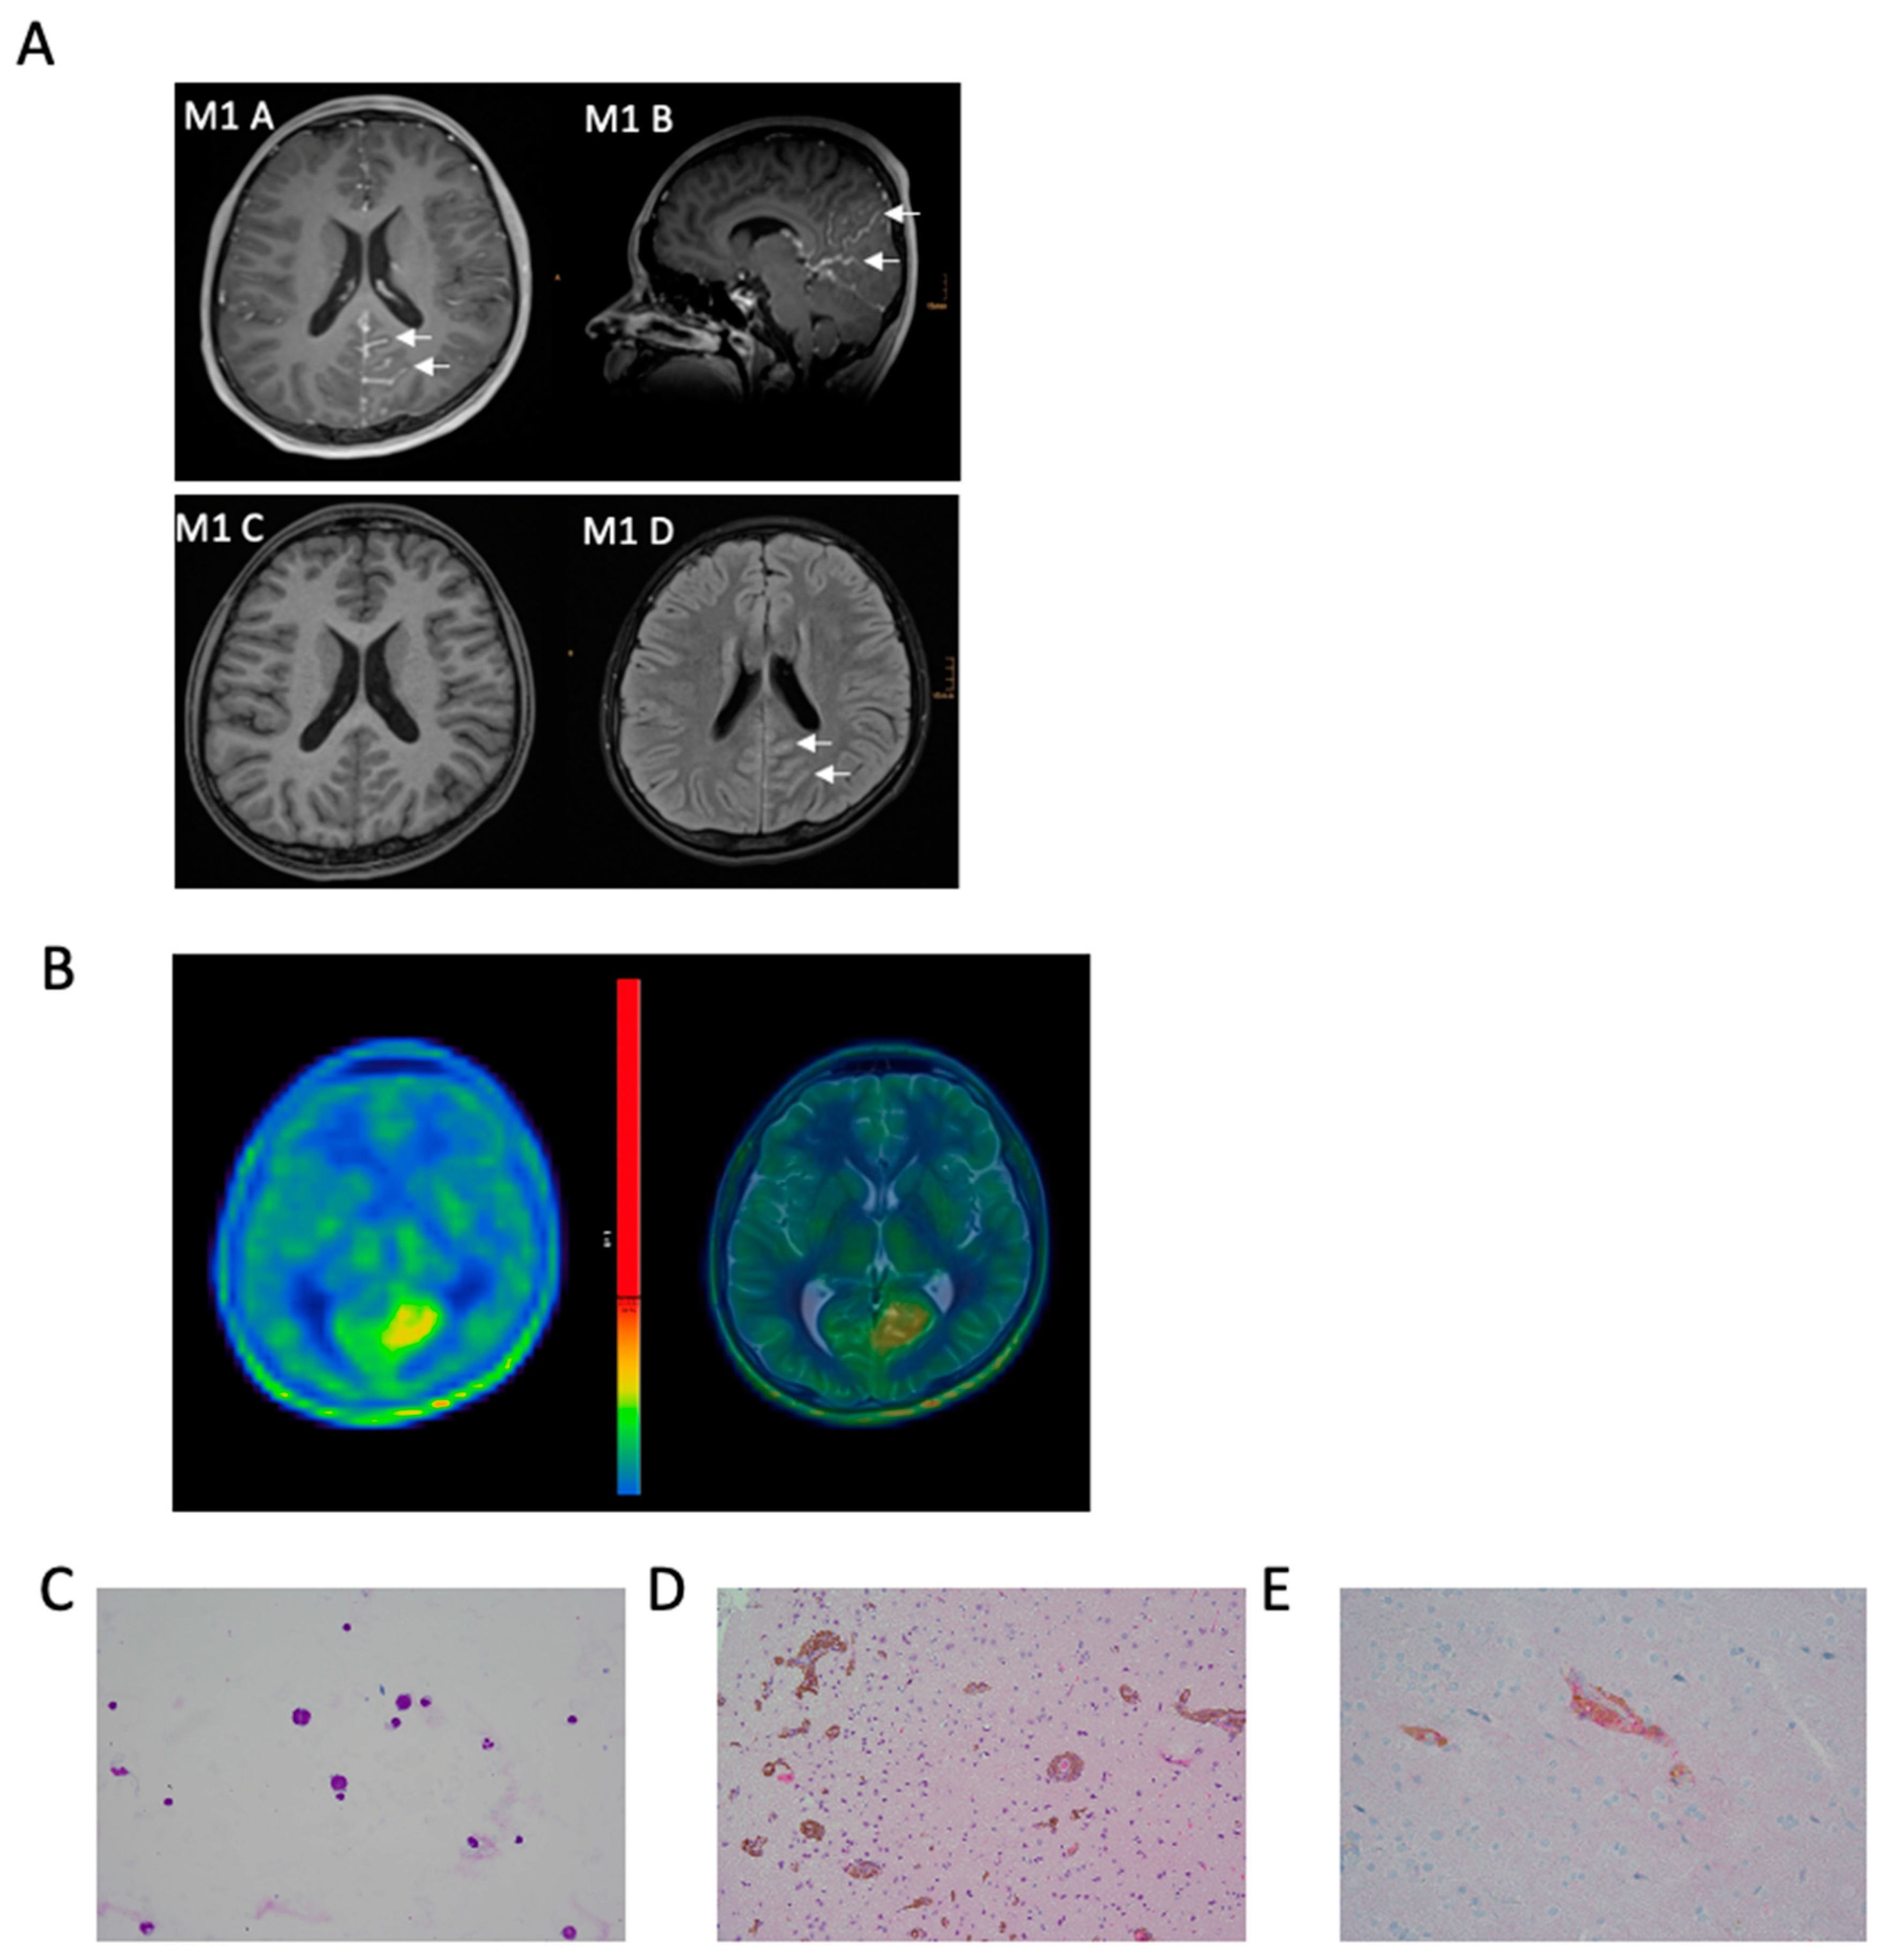

3.1. Illustrative Case